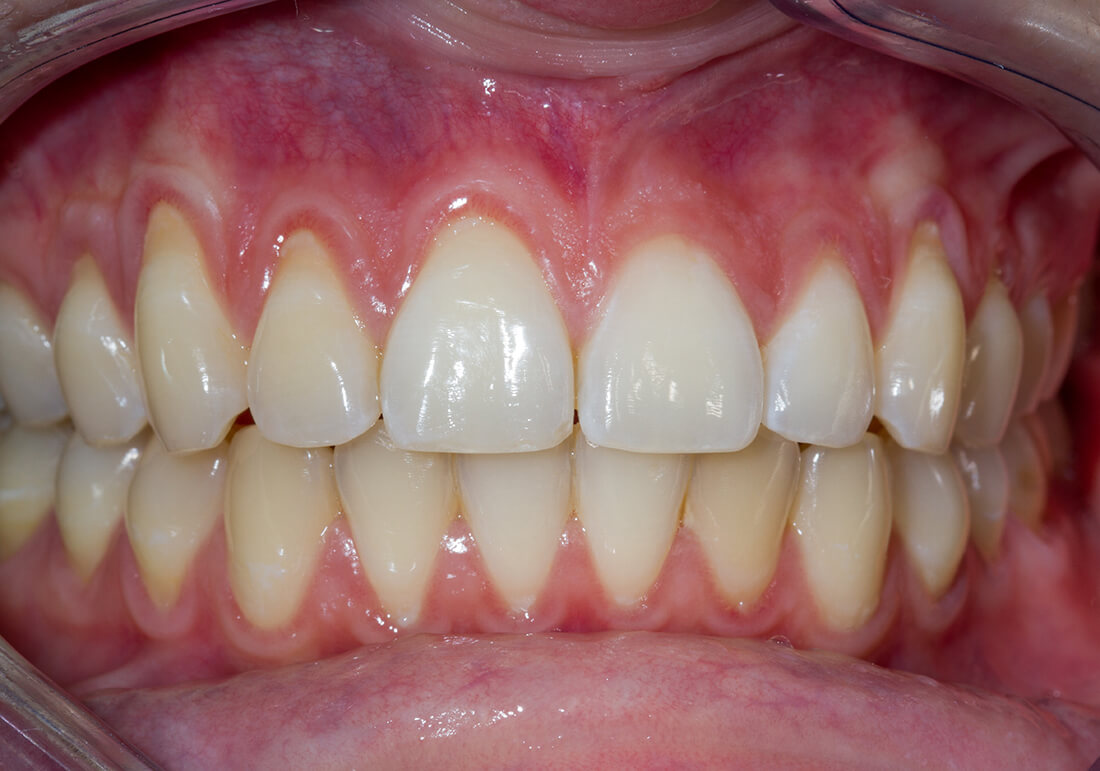

Visione schematica della Parodontite: gengive arrossate e ritirate, radice dentarie esposte e con calcoli di tartaro

Parodontite (piorrea)

La parodontite, più conosciuta con il nome di piorrea, è una malattia che nello stadio iniziale coinvolge i tessuti intorno alla radice del dente e dell’osso fino a provocare una mobilità del dente stesso, la formazione di tasche e la perdita dell’elemento dentale.

Le cause principali della malattia parodontale sono da attribuire all’accumulo di batteri tra dente e gengiva derivanti dai residui di cibo i quali, se non rimossi adeguatamente, si trasformano in placca batterica e, successivamente in tartaro che andrà ad inserirsi sotto la gengiva.

Sintomi

Anche se, come detto in precedenza, la malattia parodontale solitamente non provoca dolore, i segnenti sintomi dovrebbero essere considerati un campanello d’allarme: sanguinamento delle gengive, mobilità dentale, dolore durante lo spazzolamento, alito cattivo.